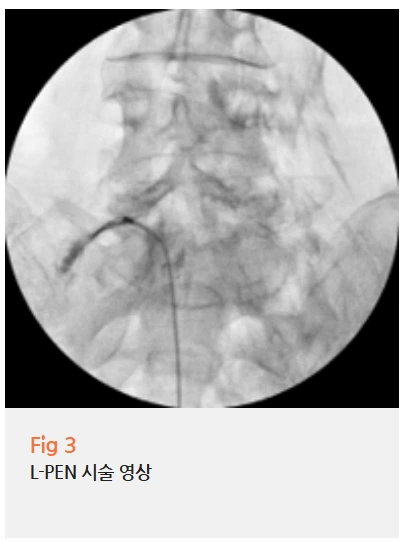

✔️ 척추 문제는 PEN 시술로 눌린 신경을 풀어주고

PEN(Percutaneous epidural Neurolysis) 시술은 경막외강 내시경 신경성형술이라고 해요.

가느다란 카테터를 척추 신경 근처에 넣어서 유착을 풀어주고,

압박받고 있는 신경 주변의 염증을 제거하는 치료예요.

%EA%B7%B8%EB%A6%BC4.png?type=w966

수술보다 부담이 적으면서도 효과가 좋아서,

고령 환자분들이나 기저질환이 있으신 분들께

자주 시행하는 치료인데요.

이 환자분도 협심증이 있으셔서

전신마취 수술은 부담스러웠거든요.